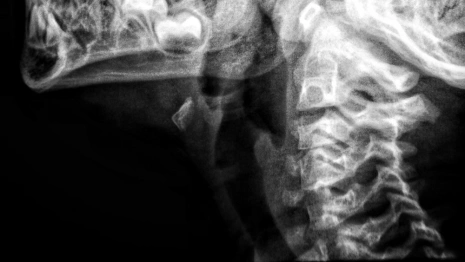

Врожденный порок развития шейного отдела заключается в сращивании и уменьшении количества позвонков. Генетическая аномалия возникает у эмбриона из-за неправильного внутриутробного развития шейных и верхнегрудных позвонков.

Для диагностики проводят рентгенографию, КТ и МРТ позвоночника, генетический анализ, расширенное обследование внутренних органов: сердца, почек, легких, головного мозга.